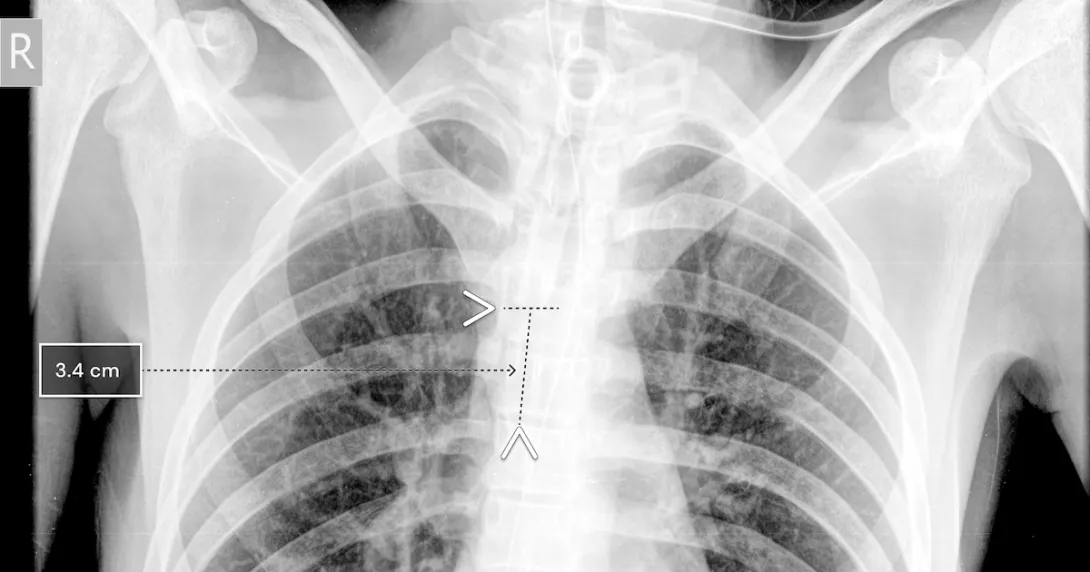

Using chest x-rays, the qXR-BT algorithm can analyze the position of the breathing tube. It automates measurement and can report accuracy to the clinician, who can then decide if the tube needs to be re-placed.